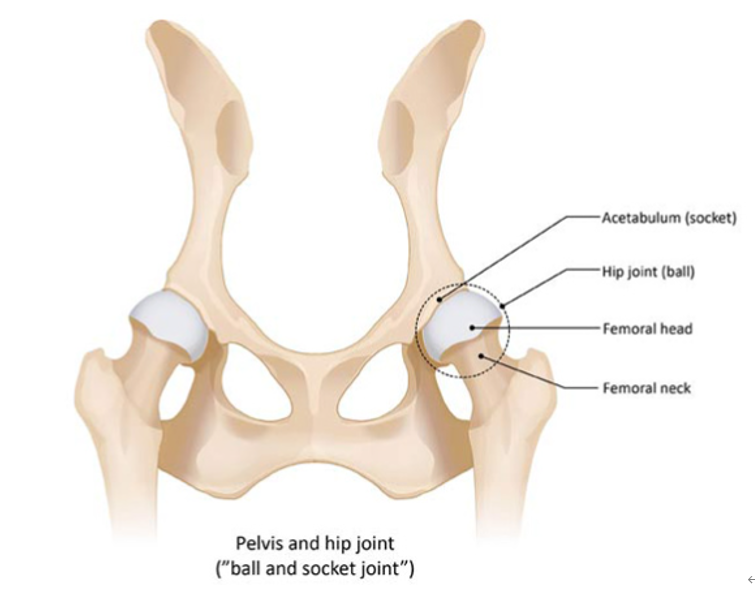

고관절이란?

골반의 고랑안에 허벅지뼈의 골두가 접해있는 관절로 뒷다리를 회전시킬 때 도와주는 역할을 합니다